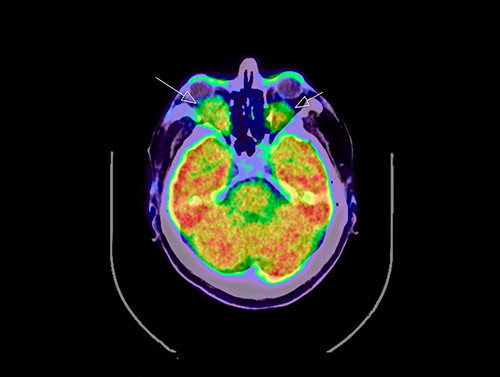

18FDG PET-CT viste økt opptak perirenalt, oppfyllinger i begge orbitae, periaortalt, i myokard og i oppfylling rundt hjertet samt i beinmargen i distale deler av begge femora og proksimale tibiae (fig 3, fig 4). I nyrene var det dilatasjon av calyces, men ikke dilatasjon av det ekstrarenale nyrebekken eller uretre. Ultralyddoppler av nyrearterier viste ikke tegn på nyrearteriestenose. I lungene var det lette mattglassfortetninger og sparsom bilateral pleuraeffusjon. Spirometri viste lett redusert belgfunksjon av restriktiv type. Ekkokardiografi viste grensestor venstre ventrikkel med god venstre og høyre ventrikkelfunksjon, i tillegg til lett perikardvæskebrem på 0,5 – 0,6 cm uten hemodynamisk betydning.

Sykdommen rammer menn hyppigere enn kvinner, og gjennomsnittlig debutalder er 55 år (16 – 80 år) (5). Mange organer kan bli affisert av sykdommen (tab 1) (5, 6). Nesten alle pasienter med Erdheim-Chesters sykdom har affeksjon av skjelettet, men bare omkring halvparten har symptomer på dette og da som oftest som smerter i knær og ankler. Typiske radiologiske funn er bilateral og symmetrisk osteosklerose i diafysen og metafysen til de lange rørknoklene, oftest i underekstremitetene. 99technetiumskjelettscintigrafi og 18FDG PET-skann vil vise økt opptak i disse områdene (7) – (9).

Erdheim-Chesters sykdom er en kronisk lidelse hvor forløp og sykdomsutfall er avhengig av hvilke organer som er affisert. Oftest ses et sykdomsforløp med affeksjon av flere organer over tid, uten spontan remisjon. Før oppstart og valg av medikamentell behandling er det nødvendig med en bred utredning for å kartlegge hvilke organer som er affisert. Både røntgen-, CT- og MR-undersøkelse kan vise sykdomsaffeksjon, men for vurdering av sykdomsaktivitet og evaluering av terapirespons er PET-skann angitt å være et godt hjelpemiddel (8).